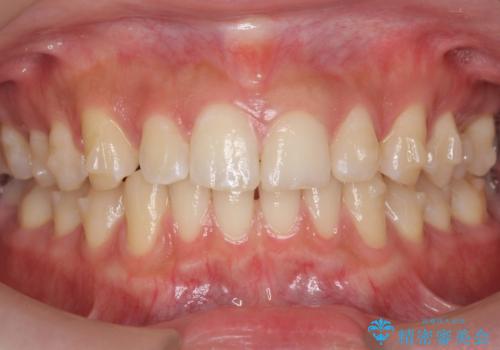

すきっ歯 セラミックで治すか矯正で治すか相談したい

- 上下の歯のすき間を気にして来院。

当初はセラミックでかぶせて上だけ治そうかな、というご希望でした。

患者様の歯は咬耗といって削れて短くなっていたため、セラミックでかぶせると隙間をうめるため横長の歯になりそうでした。術後の見た目は矯正の方が自然にみえるとお伝えしました。

また、歯ぎしりがありそうなので、セラミックにしたときにセラミックが欠けてしまうリスクもありました。